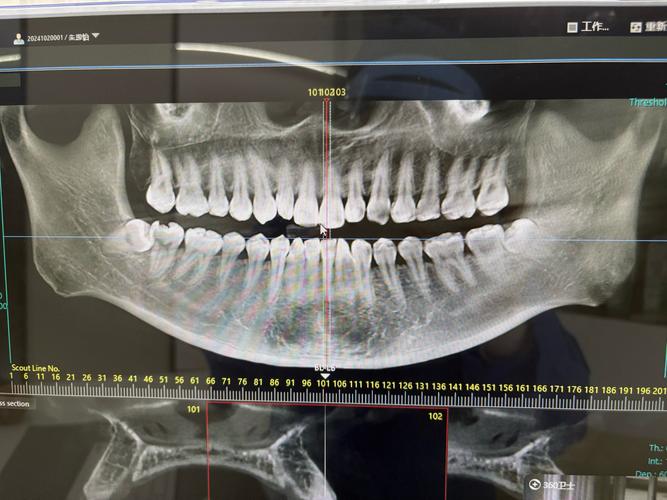

正畸治疗的核心是调整牙齿位置、改善咬合关系、协调颌骨发育,这需要全面了解牙齿排列、牙根形态、牙槽骨状况、颌骨大小与位置关系,以及面部软组织轮廓,仅通过口腔检查或模型分析,无法获取骨骼、牙根等深层结构信息,而X光影像能提供“全景视角”:例如全景片(曲面断层片)可观察全口牙齿的萌出方向、牙根长度、是否有埋伏牙或牙根吸收;头颅侧位片能测量骨骼角度、牙齿与颌骨的相对位置,用于制定精准矫治方案;复杂病例可能还需CBCT(锥形束CT)获取三维数据,评估骨量、牙根与神经管关系等,这些影像是正畸诊断的“导航仪”,直接关系到治疗方案的合理性和效果。